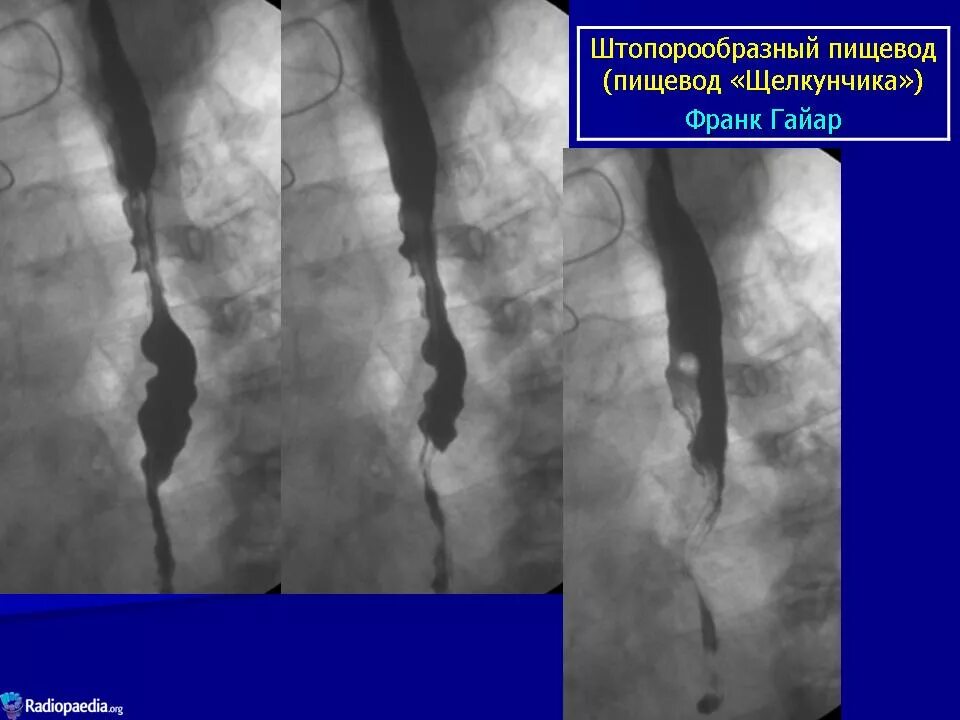

Кольцо шацкого в пищеводе что это